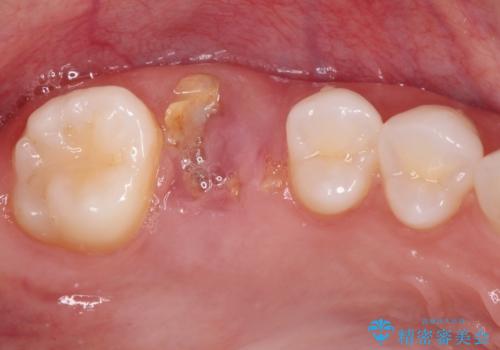

- 歯がほとんどなくなってしまうまで虫歯を放置してしまったとのことで来院された患者様です。

抜歯が必要であることは患者様自身も理解されており、インプラントによる欠損補綴治療を希望されていらっしゃいました。